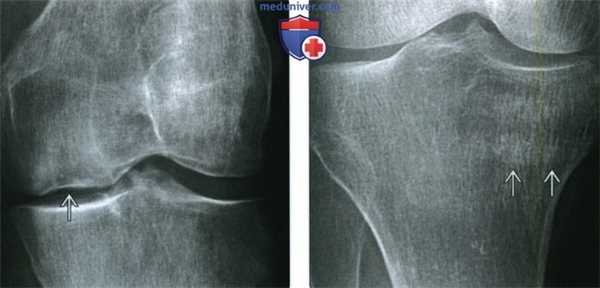

(Слева) Рентгенография в ПЗ проекции: коленный сустав с остеопен ией вследствие остеопороза. Стрессовый перелом медиального мыщелка бедренной кости осложнился коллапсом составной поверхности.

(Справа) Рентгенография в ПЗ проекции: определяется стрессовый перелом медиального проксимального отдела большеберцовой кости. Перелом представляет собой размытую горизонтальную линию с нечеткими контурами в типичном для стрессового перелома месте.